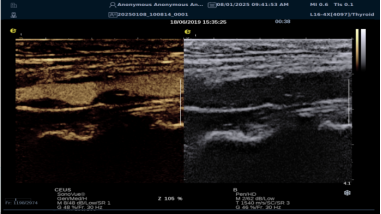

RawVisionTM Plaque技术(RVP

RVP 是世界领先的颈动脉斑块自动定量分析成像模式,依托 RawVisionTM原数平台强大的原始射频数据采集与分析能力。其优势显著:

? 可视化呈现方面,能分析斑块在特定条件下内部纹理变化,生成可视化参数成像。医生可依据颜色辨别易损与稳定斑块,并进行定量测量。

image.png

? 定量评估上,提供 CNTENTNRTCPT 等指标和参数,为监测老年颈动脉斑块风险提供客观准确依据。

? 借助 AI 自动分析,可快速筛选诊断,提升脑卒中筛查效率,有望重塑易损斑块临床诊断流程。

? 具备技术升级潜力,支持高端科研,能挖掘更多诊断参数,满足临床需求。

相比传统超声弹性成像技术,RVP 利用颈动脉搏动采集数据,避免了操作者施压等主观因素干扰,数据处理更精准,结果重复性佳,不受操作者差异影响。